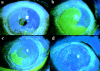

Figure 4

(a) Broad beam slit lamp photograph of a patient with extensive conjunctivalisation of the cornea. Only a small area of the corneal surface, corresponding to one and a half clock hours of the inferotemporal limbus, is covered by corneal epithelium. Note the well defined line of demarcation (arrowheads) between corneal and conjunctival epithelium. The patient's vision was 6/18 (×10). (b) Fluorescein stained picture of the cornea immediately after removal of conjunctival epithelium over and around the pupillary area (×6). (c) The same eye on day 2 following removal of conjunctival epithelium. Note that the pupillary area is being covered by migration of corneal epithelium from the small area of preserved corneal epithelium illustrated in (a) (×6). (d) On day 5 following removal of conjunctival epithelium, healing is almost complete and the pupillary area is covered by healthy corneal epithelium. The visual acuity improved to 6/9 (×6).